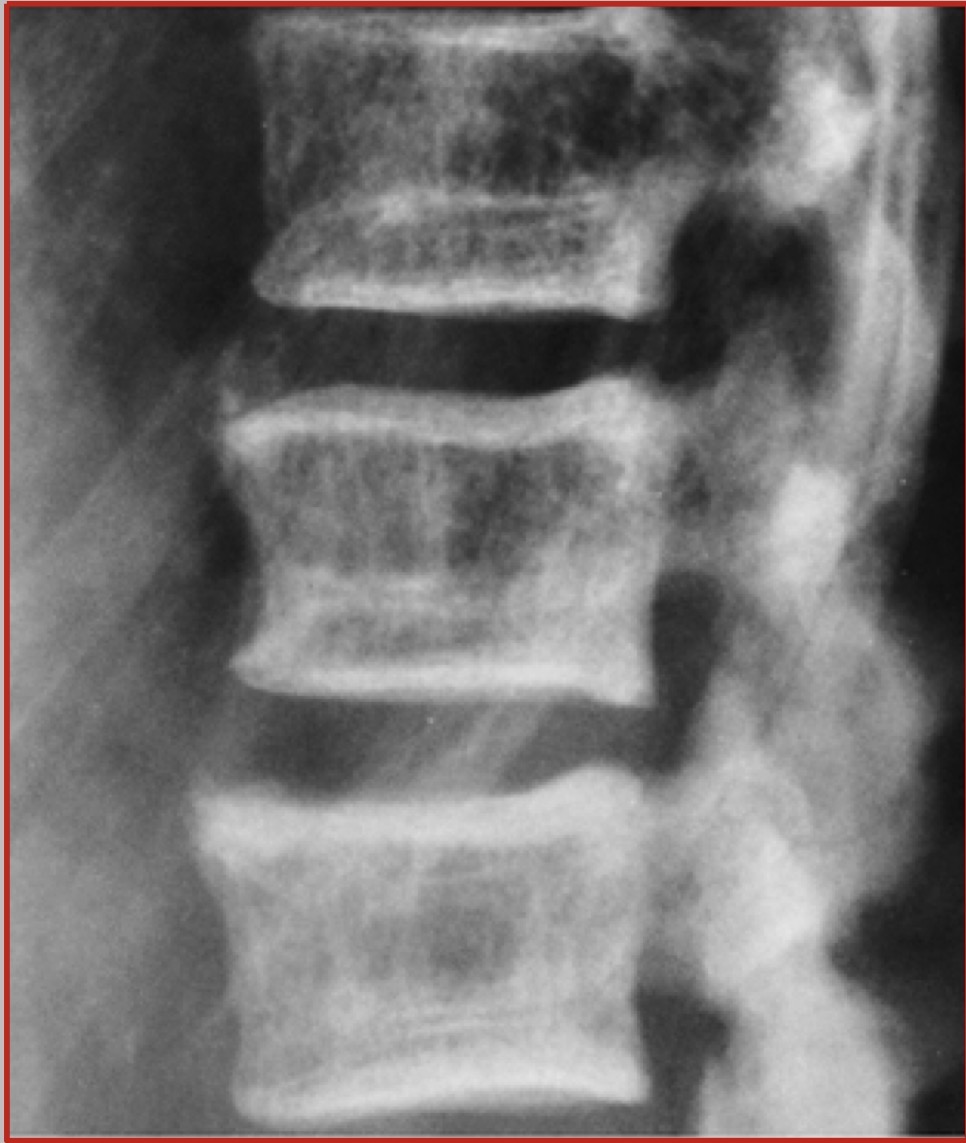

_________ refers to bones that are brittle and fracture.

Osteoporosis

________ refers to bones that are soft and bend.

Osteomalacia